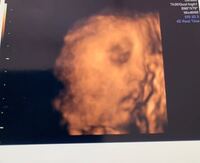

32週の4dエコー写真です この写真から鼻が高い 低い目は大きい 小さい顔 Yahoo 知恵袋